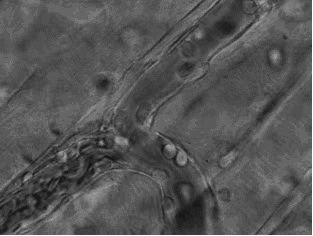

这张动图显示的是免疫细胞

逐渐聚集到一只秀丽隐杆线虫周围

并对它进行攻击的过程。

有“成千上万”的免疫细胞围聚在线虫周围,

就像一群蚂蚁,善打“包围战”。